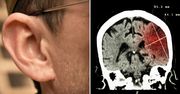

Naukowcy: wystąpienie udaru może zależeć od kształtu ucha